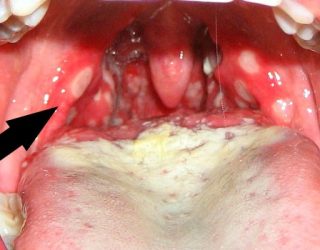

При более выраженном воспалительном процессе обнаруживаются интенсивные отложения в зонах патологии. Они представляют собой бляшки белого цвета, которые накрывают заднюю стенку глотки и небные миндалины. Такой клинический признак очень характерен и легко узнаваем на фотографиях пациентов.

- Внешний вид горла. Если речь идет о бактериальной форме заболевания, гнойники обычно образуются только на небных миндалинах, в то время как покраснение распространяется на небные дужки и мягкое небо. При грибковой форме ангины вся поверхность глотки покрывается грибковым налетом.

- Размер, область распространения и характер белого налета. При грибковой форме он имеет вид творога, в то время как при бактериальной форме проявляется в виде гнойников. В первом случае налет локализуется на языке, небе и миндалинах, а во втором – только на миндалинах. После удаления налета при грибковой ангине остаются кровоточащие ранки, в то время как при бактериальной ангине слизистая просто краснеет.

Если на слизистой оболочке появляется белый налет, напоминающий творог, то врач обязательно проводит взятие мазка из зева. Даже если налет незначительный, все равно стоит провести лабораторный анализ. Чтобы взять мазок из зева у ребенка, его нужно посадить на стул и попросить открыть рот. Кончик языка фиксируется шпателем, а стерильным ватным тампоном проводят по горлу. Взятый материал отправляют в лабораторию. Если ребенок слишком маленький, то родители берут его на руки. Одной рукой держат его корпус, а второй – голову. Ножки ребенка зажимаются между своими ногами.